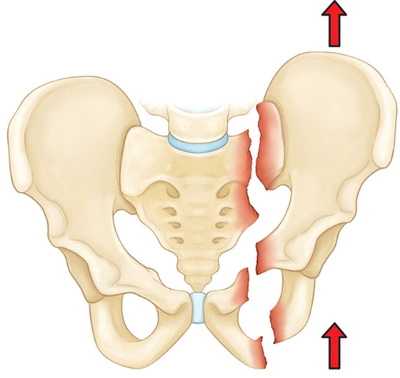

Нестабильные переломы. Данный тип переломов характеризуется нарушением целостности тазового кольца как минимум в двух точках, при котором анатомия таза, как правило, нарушается (происходит смещение фрагментов). Чаще всего такие переломы возникают вследствие высокоэнергетической травмы. К нестабильным переломам относят следующие:

На рисунке — Вертикально-нестабильный перелом. При данном переломе одна половина таза смещается вверх